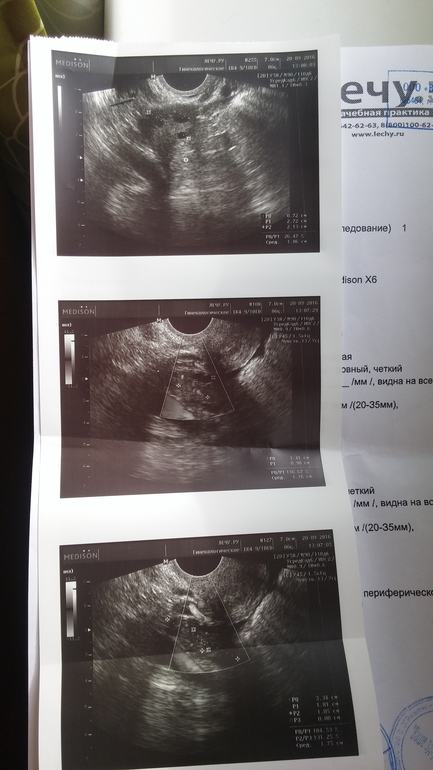

Девочки,сходила я значит на фолликулометрию и чет расстроилась...О подтвердили. Предыстория : сегодня у меня 25ДЦ и 5ДПО. Все в норме,жт есть,но его немного! Врач сказал сдать кровь на прогик-уже сдала,завтра заберу результаты. Теперь я так переживаю,что проблемы с прогиком и пролет в этом месяце...единственно что врач сказал,что ДПО прошло немного и возможно из-за этого жт нет в нужном кол-ве. Девочки,поддержите ((((неужели это пролет...p.s анализы (под кат)

подожди расстраиваться!!!!все хорошо-еще не понятно.жт можно подрастить с помощью дюфа.....если прогик не обнадежит да и детке есть где крепиться ...правда не вижу эндометрий какой

Эндометрий 8,8 :) сказали здесь все хорошо...вот только жт...